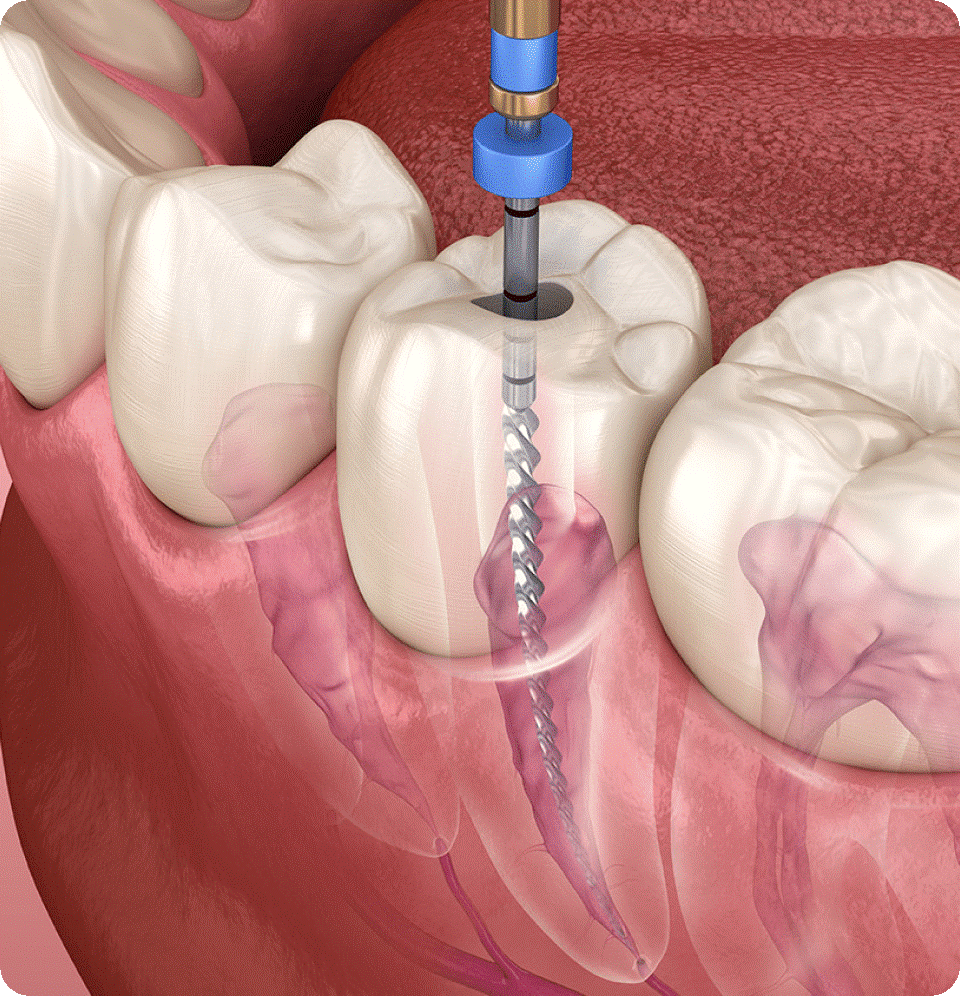

It includes a wide range of procedures, including teeth extractions, dental bone grafts, periodontal (gum) grafts and corrective jaw surgery.

- Periodontics

- Gum disease